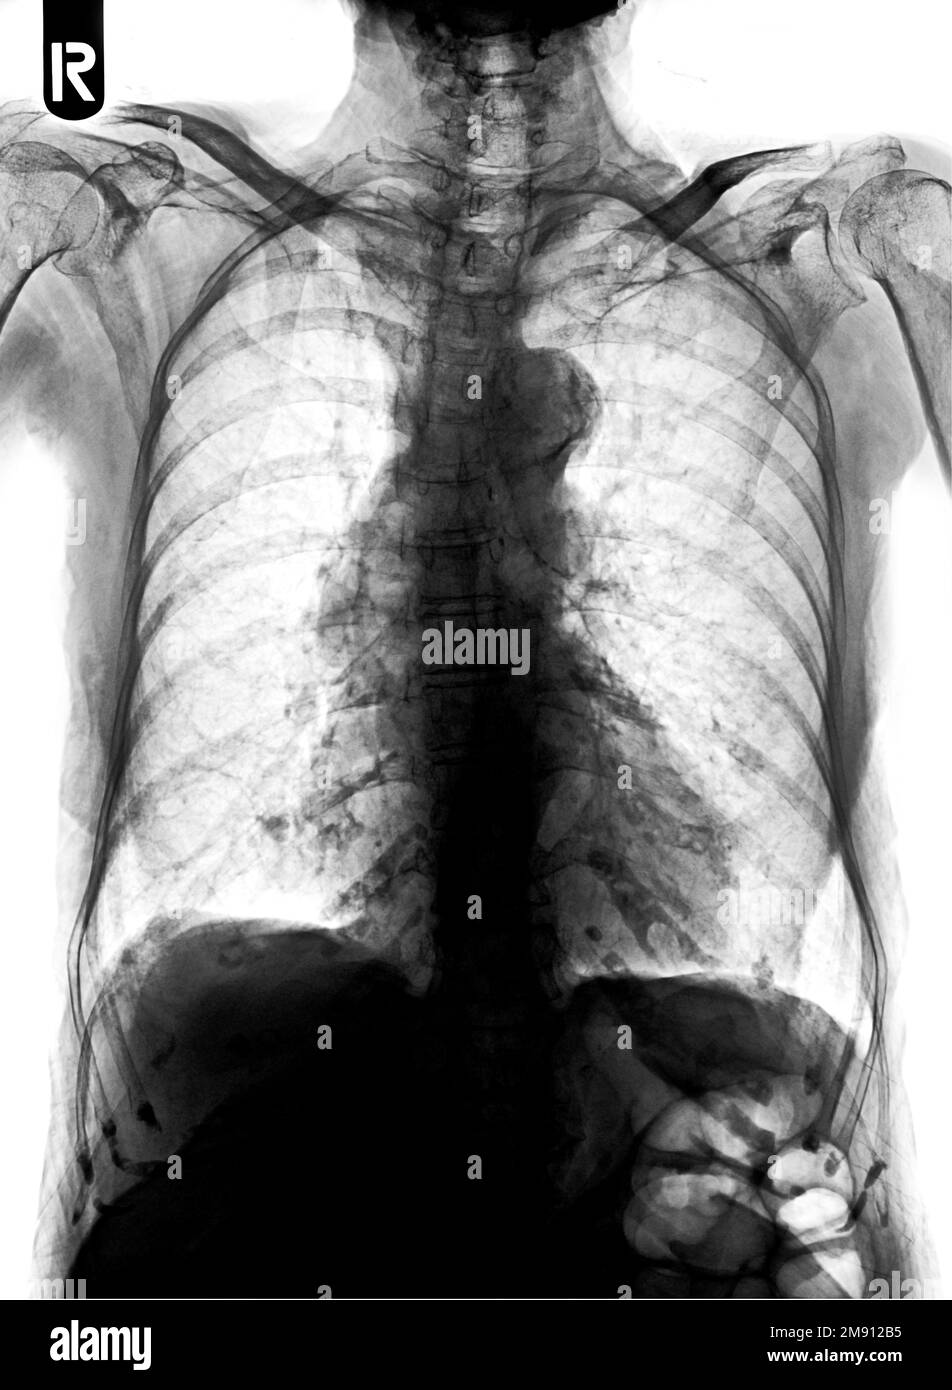

from www.cureus.com

Adenocarcinoma of the Lung Presenting with Intrapulmonary Miliary